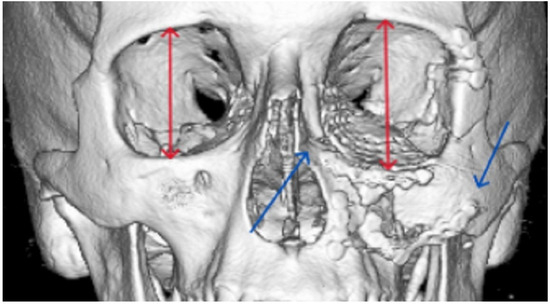

| Zygomatico–orbital complex * | 6 | 4 | 6 inadequate reductions | ||

| Le Fort ** | 4 | 1 (Le Fort III) | 4 inadequate reductions | ||

| Orbit | 4 | 0 | 3 inadequate reconstructions of orbital floor fractures, 1 orbital deformity due to inadequate reduction of the zygomatic bone | ||